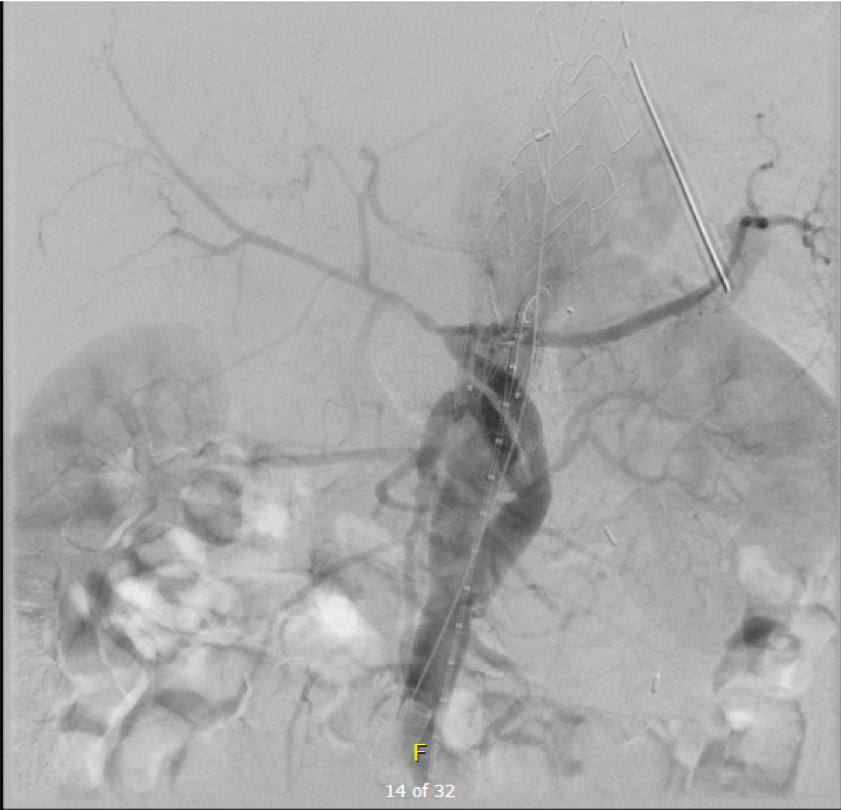

Arteriography from femoral access showed an occlusion of the SMA beyond the middle colic artery, a typical pattern for an embolism that occurs when embolism lodges distally and propogates proximally (image below).

I got Glidewire access into the ileocolic terminus of the SMA, exchanged for a Rosen wire, over which I placed an 8F sheath into the proximal SMA. This was a rather large sheath meant to catch thrombus as I suctioned it out with a 6F Penumbra catheter. This is another technique I borrowed from the neurointerventionalists. Whenever a stroke alert is going on, curiosity drives me to peak in and see what marvelous gadget or gewgaw they are using, and I was impressed by how efficiently the neurointerventionalists were able to get to the smallest thrombus in the furthest branch vessels. I was prepped for open thrombectomy, consented for bypass if necessary, but having experience in suctioning clot through single catheters and sheaths, I thought the simple design of the Penumbra and its efficacy in the cerebral system could easily translate into the mesenteric.The problem with open thrombectomy is the inability to see if you have cleared thrombus from all the branches unless you do an arteriogram after you’ve completed your procedure. This may be a significant contributor to the 20-30% bowel resection rate that occurs on second look laparotomy in my old paper and in the literature since its publication.

The Penumbra was effective in removing much of the fresh thrombus, but I was also cognizant of the fact that pulling out the catheter will draw clot into the 8F sheath that did not make it into the catheter. I placed a wire, and removed the sheath to expel much of the bulky thrombus (picture below).